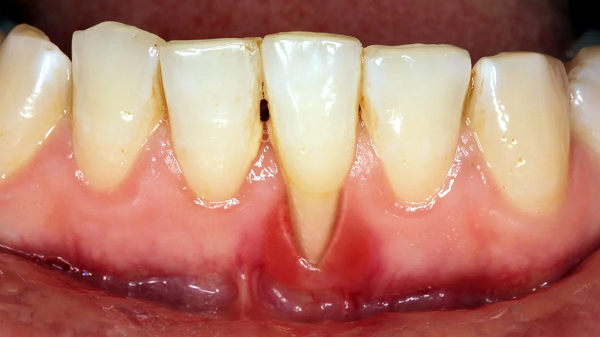

Tiêu xương răng là tình trạng mất dần mô xương xung quanh chân răng do vi khuẩn gây ra, thường xảy ra khi viêm nướu không được điều trị kịp thời. Quá trình này bắt đầu từ viêm nướu, nếu không được chăm sóc đúng cách, viêm nhiễm có thể lan sâu vào các mô xương, dẫn đến tiêu xương và mất răng. Triệu chứng của tiêu xương răng bao gồm chảy máu nướu, hơi thở hôi, răng lỏng lẻo, tụt nướu và đau nhức. Việc phát hiện và điều trị sớm tiêu xương răng giúp ngăn ngừa các biến chứng nghiêm trọng.

- Lợi tụt xuống: Lợi bị tụt xuống, lộ ra phần chân răng, làm răng trông dài hơn bình thường.

- Chảy máu lợi: Lợi có thể bị chảy máu khi đánh răng hoặc dùng chỉ nha khoa.

- Nướu bị sưng tấy: Nướu có thể sưng, đỏ và có thể kèm theo cảm giác đau.